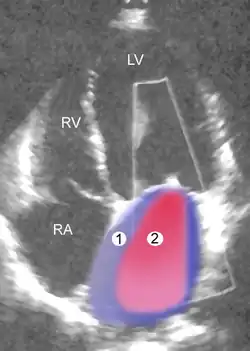

Mild mitral regurgitation. The colored cloud symbolizes the return blood flow. 1. left ventricle, 2. left atrium

1 Left atrium (LA) – 2 MR Jet, LV Left ventricle – RV Right ventricle – RA Right atrium